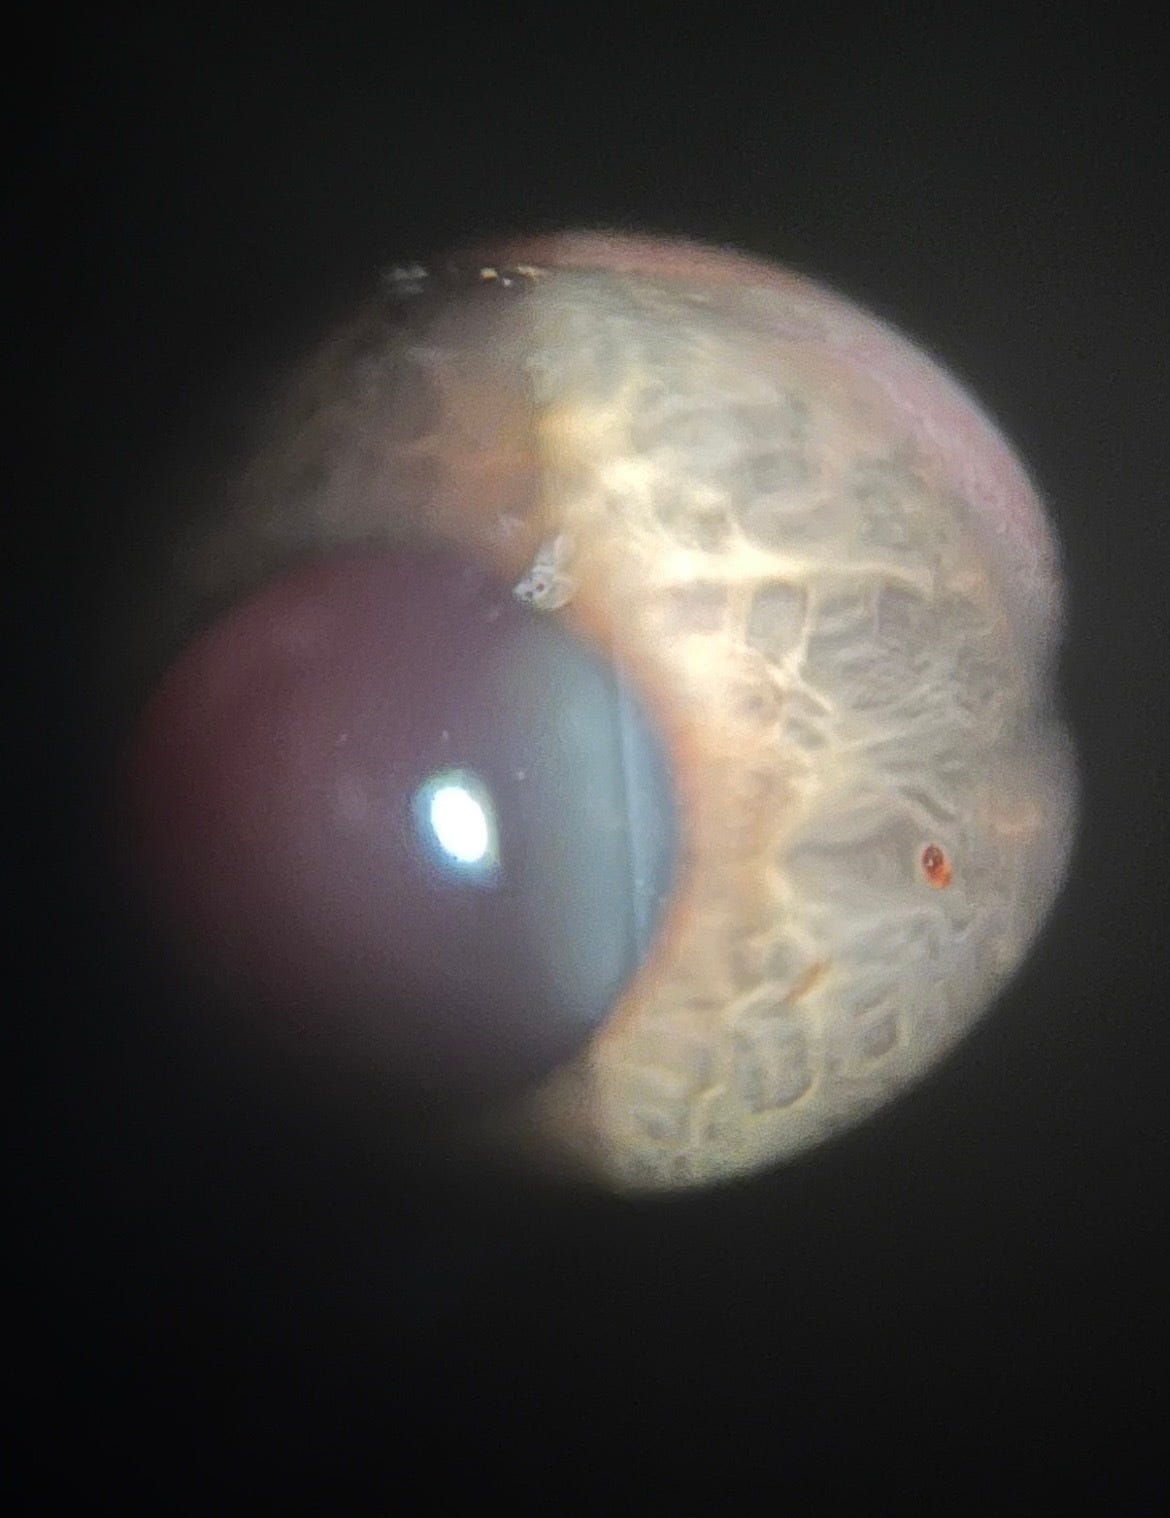

I’m staring into this bright light and she says “hahahahahaha you have a piece of rusty metal inside your eye.” (Yes, she actually laughed about it.)

She was pretty funny. She smiled and said “yeah, can I take a picture?”

She did a quick minor procedure to remove the metal and I’ll be fine. She said there’s still a piece of microscopic metal that she couldn’t get. She said it would probably heal over but when I go back today she will try to remove it.

Check it out.